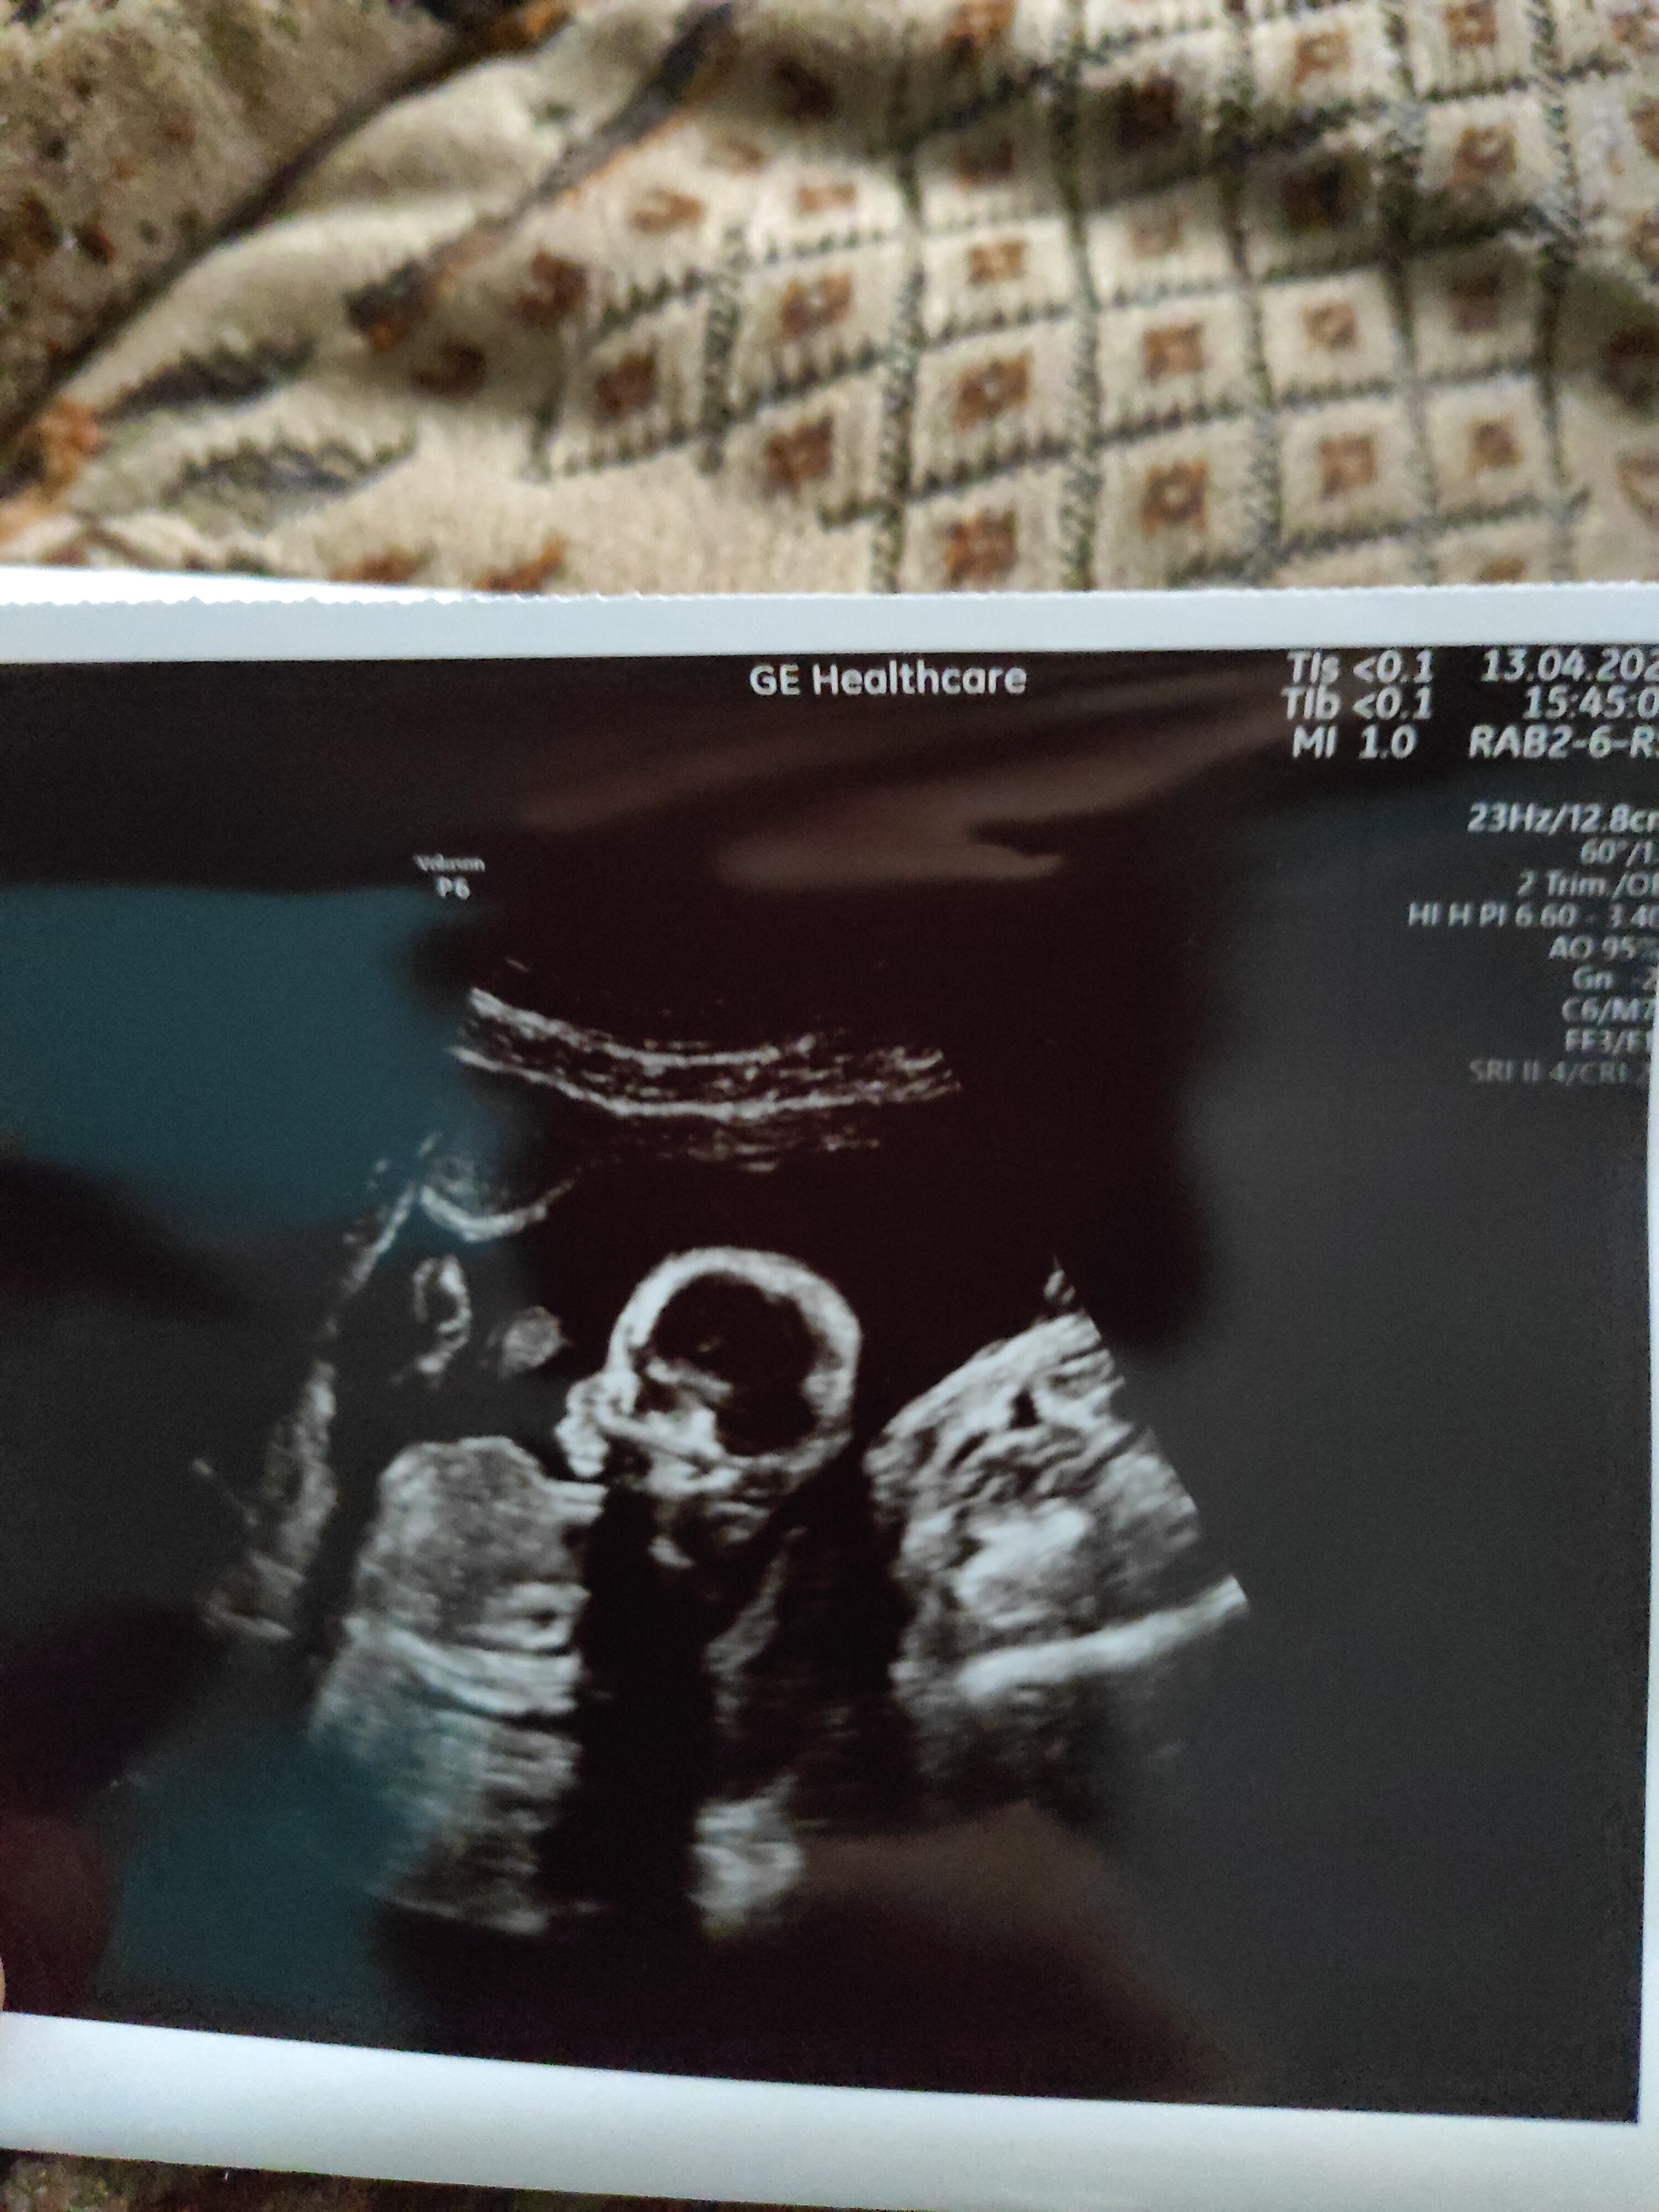

Tak chlopakI jak? Znasz już płeć? Ja czysto teoretycznie obstawiam dziewczynkę.![]()

Gratuluję.Tak chlopak

Nie widać nuba. Który to tydzień ciąży? Dziecko wygląda na małe.Witam czy jest ktoś kto widzi płeć z tych zdjęć

To w tym wieku już można robić zdjęcia pupki i płci od dołu. Będzie wszystko dobrze widać.15 tydz